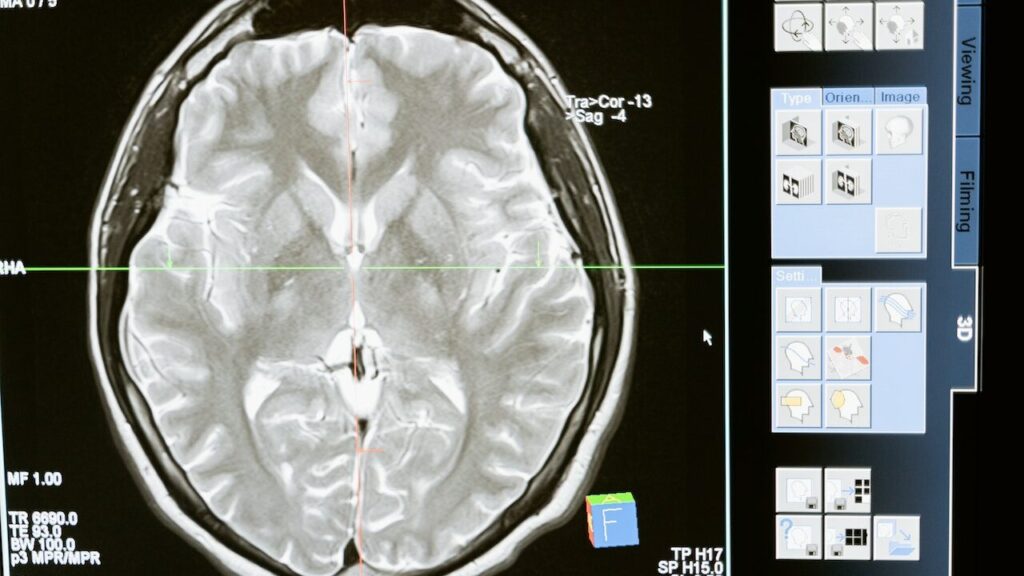

- Ультразвукове дослідження нирок дає змогу візуалізувати стан і аномалії органів.

- У деяких випадках для більш детального обстеження уролог призначає комп’ютерну томографію (КТ).